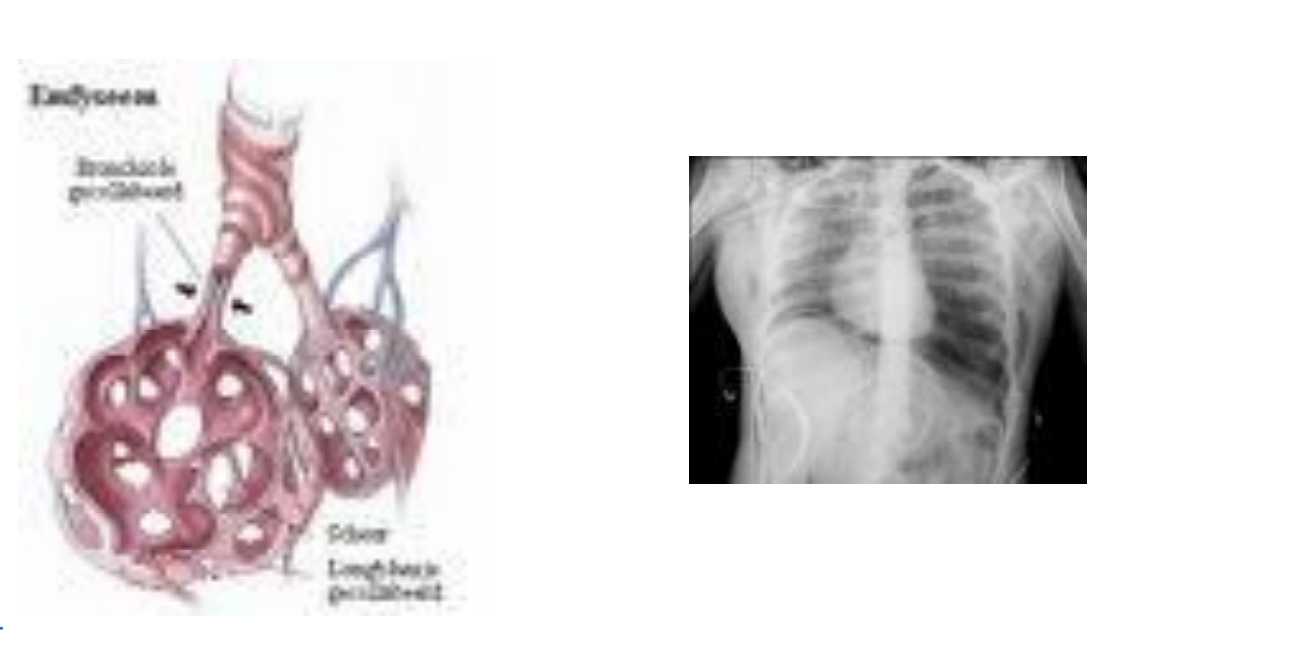

DESTRUCTIEF LONGEMFYSEEM

Destructie van alveolaire septa en soms respiratoire bronchiolen → ontstaan van grote luchtruimten = hyperinflatie

Longen zien er bleek en opgeblazen uit

Destructief Longemfyseem - Kliniek / Symptomen

Dyspnoe (kortademigheid)

Typische thoraxveranderingen:

Tonvormige thorax , Vooruitspringend sternum ,Opgetrokken schouders

Auscultatie: verminderd ademgeruis, vaak verlengd exspirium

Diagnose Destructief Longemfyseem

Klinisch onderzoek

Röntgenonderzoek: hyperinflatie van longen, laagstaande diafragmakoepels, brede tussenribruimten

Spirometrie: functionele beperking en luchtwegvernauwing